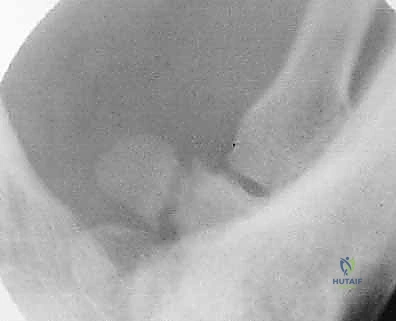

- الأشعة السينية بوضعيات خاصة: أخذ صور بأكثر من زاوية لفك تراكب العظام.

3. لماذا يصعب تشخيص كسور الرسغ في البداية؟

عظام الرسغ صغيرة جداً ومتراكبة فوق بعضها البعض. في الأشعة السينية العادية (2D)، قد تخفي عظمة ظلاً لعظمة أخرى، مما يجعل الشروخ الدقيقة غير مرئية. لذلك يعتمد الدكتور هطيف على الفحص السريري الدقيق والأشعة المقطعية (CT).